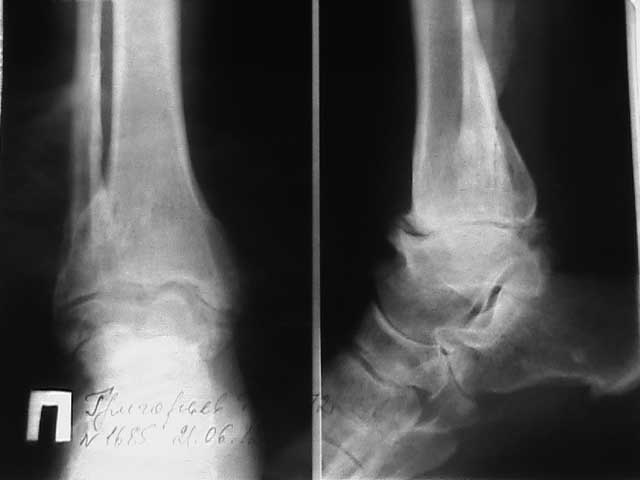

Больной М, 40 лет, повышенного питания,13.01.2005г. получил травму:закрытый косой оскольчатый перелом малоберцовой кости в н/3, поперечный перелом внутренней лодыжки правого голеностопного сустава, разрыв ДМБС, подвывих стопы кнаружи

(диагноз из вып.эпикриза ГорБ-цы, где проводилось лечение).18.01.05г.операция-остеосинтез внутренней лодыжки винтом, малоберцовой кости пластиной, фиксация ДМБС болт-стяжкой. П/о период гладкий.19.01.06г. в связи с консолидацией переломов (Rg-грамм нет) выполнено удаление металлоконструкции. В дальнейшем наблюдался в пол-ке по поводу п/травм.артроза правого г/ст сустава. На сегодня (впервые попал к нам) жалобы на ограничение движений, боли при ходьбе, периодические отёки. Объективно: хромает на правую ногу (без доп. опоры), контуры сустава сглажены, правая стопа незначительно пронирована, пальпация безболезненная, окружность н/3 голени (в проекции лодыжек) +2см, движения в суставе ограничены за счёт тыльного сгибания( 110 градусов). Больной хочет восстановить объём движений и избавиться от болей. Что можно и необходимо сделать в этом случае?